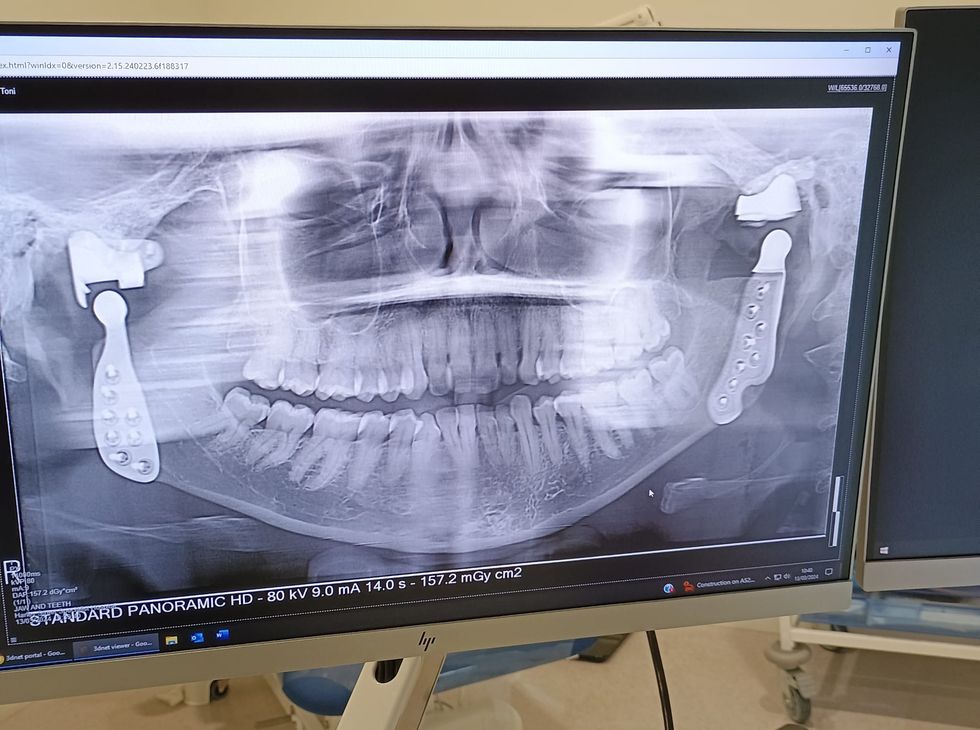

Toni Bull was given the nickname Titanium Toni – which she said perfectly “encompasses what I am now” – by one of her friends as she has two titanium jaw joints following years of issues including clicking and reduced movement, as well as countless medical appointments.

In March, her left jaw joint was removed and replaced with a titanium joint, while in February 2022, her right jaw joint was swapped out for a titanium joint at Harley Street Specialist Hospital, in London.